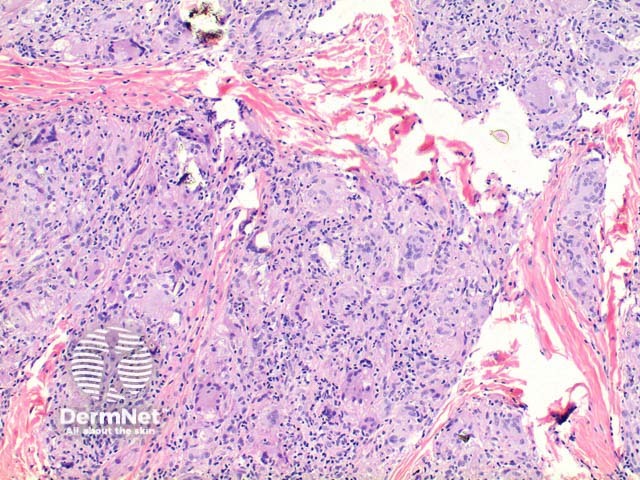

Sarcoidosis is a multisystem disease characterised by granulomas in various organs. Characteristically, these are non-caseating epithelioid granulomas (a pathological description distinguishing sarcoidal granulomas from the caseating or cheese-like granulomas seen in tuberculosis).

Sarcoidosis pathology